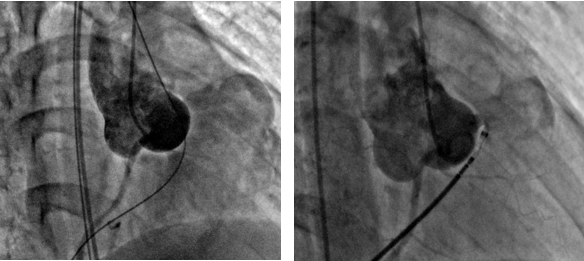

Для дальнейшего исследования пациент направлен на катетеризацию сердца. Исследование выполнено на спонтанном дыхании. Сосудистый доступ осуществлялся через правую бедренную артерию и вену, в дальнейшем для ангиографического контроля использован доступ через левую бедренную артерию. Диагностические катетеры 5 Fr. После выбора наиболее удачной позиция для ангиографии RAO 44- CRA 25, Выполнено контрастирование корня аорты. Отмечен сброс контраста в ПЖ в непосредственной близости клапана ЛА. Коронарные артерии без особенностей (рис 4).

Рисунок 4.

Чрез-артериальным доступом через дефект проведен проводник 0,035, кончик проводника направлен в ствол ЛА, выполнен захват проводника ловушкой типа «лаcсо», проводник выведен через венозный доступ, таким образом сформирована артериовенозная петля. Методика закрытия данного дефекта не отличалась от закрытия стандартного ДМЖП, однако учитывая непосредственную близость устья ПКА, принято решение имплантации PDA окклюдера, так как диск окклюдера несколько меньше и тоньше чем у VSD окклюдеров. Венозным доступом по проводнику проведено доставочное устройство SFP 6 Fr, по которому доставлен PDA окклюдер «LifeTech»XJFD0608. Дистальный конец окклюдера расположен в правом коронарном синусе, а тело окклюдера закрывает полость дефекта. На контрольной ангиографии сброса контраста через тело окклюдера не выявлено. Правая коронарная артерия не скомпрометирована. Давление в ПЖ 33/2 торр. Осложнений во время процедуры не было. Время операции 17 мин, рентгеноскопии 9 мин.( Рис. 4,5)

Рисунок 5. Окончательный вид операции.